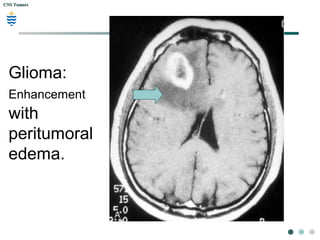

Glioma:

Enhancement

with

peritumoral

edema.